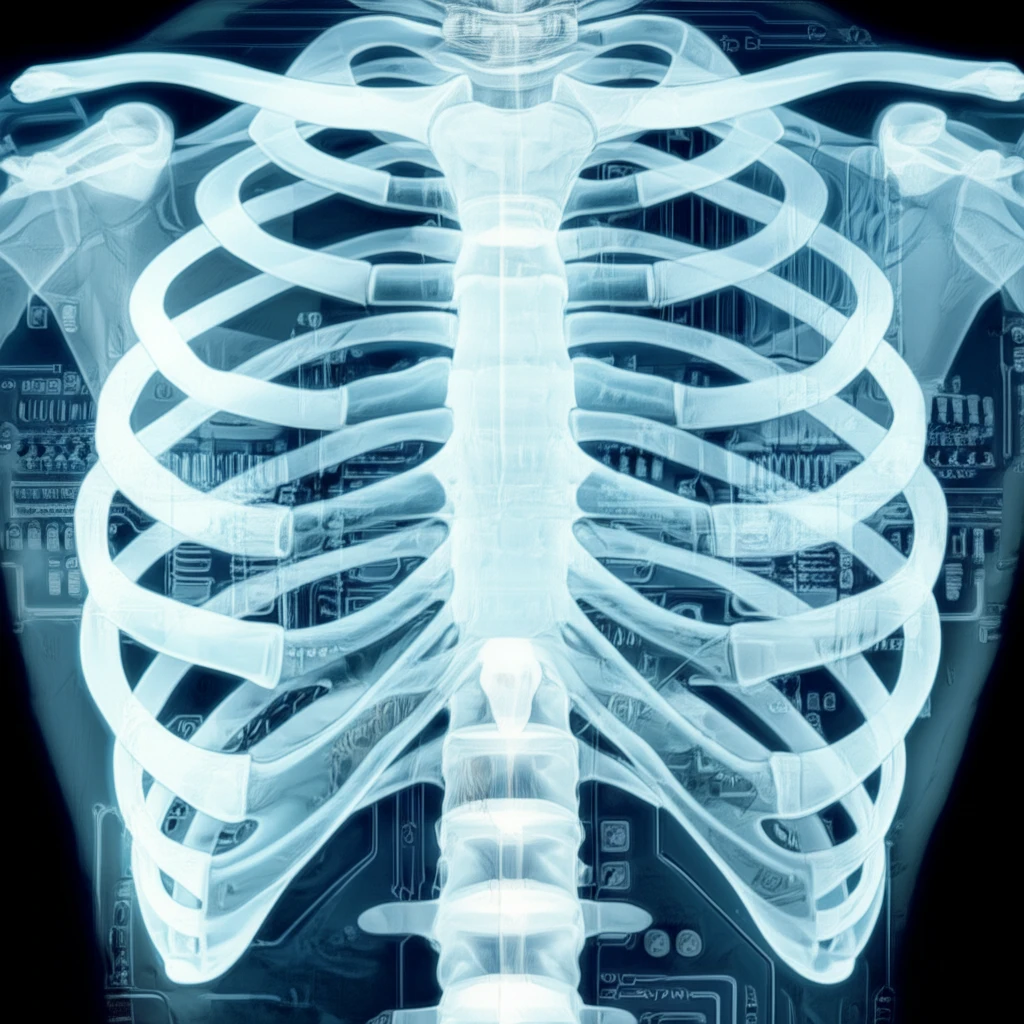

Rib fractures are a common injury, often resulting from falls, car accidents, or sports-related trauma. Detecting these fractures accurately is crucial for managing pain, preventing complications like pneumonia, and identifying underlying issues. However, spotting rib fractures on chest X-rays can be challenging, even for experienced doctors.

Traditional methods of detection heavily rely on the radiologist's expertise and the quality of the X-ray image. This can lead to missed fractures or delayed diagnoses, especially since ribs are small, overlap each other, and can be obscured by other structures in the chest. Up to 50% of rib fractures can be missed with radiography alone, putting patients at risk for further complications.

Now, researchers are exploring new technologies to aid in rib fracture detection. One promising approach involves using computer-aided methods to analyze chest X-rays. These methods use local texture and shape features to quantify the characteristics of broken ribs. By using these measurements, medical professionals can accurately identify the fractures for quick and effective treatment.